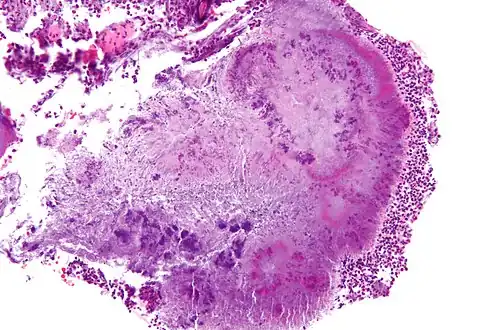

| High-magnification micrograph of a "sulfur" granule formed by Actinomyces in the mandible, H&E stain | |

Actinomyces bovis is a branching, Gram-positive, rod-shaped bacterium of the genus Actinomyces.[1] It is the causative agent of lumpy jaw in cattle, and occasionally causes actinomycosis infections in humans.[3] A. bovis normally populates the gastrointestinal tract of healthy ruminants, but is opportunistic in nature and will move into tissues through ulcerations or abrasions of the mucosa to cause infection.[4] The disease occurs when there is physical damage to the tissue of the mouth, allowing the bacteria to colonize the deep tissue and bone, typically affecting the mandible and maxilla.[5] Actinomycosis is pathognomonic for abscesses containing "sulfur" granules, and its colonies appear basophilic with club-shaped reaction products on a histological preparation.[6][7] Lumpy jaw is commonly treated with broad-spectrum antibiotics with varying success,[8] and can be a major economic loss for producers in countries where it is endemic.[9] Because this organism is zoonotic, it is a human health concern and can cause granulomas, abscesses, skin lesions, and bronchopneumonia.[4]

To diagnose lumpy jaw, the fluids exuding from the bony lump or other abscesses are sampled or aspirated if the infection has not broken through the skin.[18] Tissue samples from the lesion can be examined by histopathology after being embedded in paraffin wax, cut into 4- to 5-mm sections, and stained with hemolysin and eosin stains.[17] The clubs could also be stained by carbol fuchsin with decolourisation by weak hydrochloric acid and counter-staining with methylene blue, Van Gieson's stain, or aniline gentian violet followed by treatment with alcohol.[20] A. bovis can be identified histologically by its basophilic colonies and club-shaped reaction product visible in neutrophilic granulomatous lesions.[17] The club-shapes, also called Spendore-Hoeppli proteins, seen on histological slides are the result of the bacteria being encased in a calcium-phosphate protein complex, as the host attempts to wall off the infection.[17] Another diagnostic feature is the presence of "sulfur" granules,[6] which is pathognomonic for actinomycosis.[17] These granules are small, yellow clumps of exudate that are visible to the naked eye with a similar appearance to grains of sulfur, and are mainly composed of bacterial filaments and host calcium phosphate.[17]